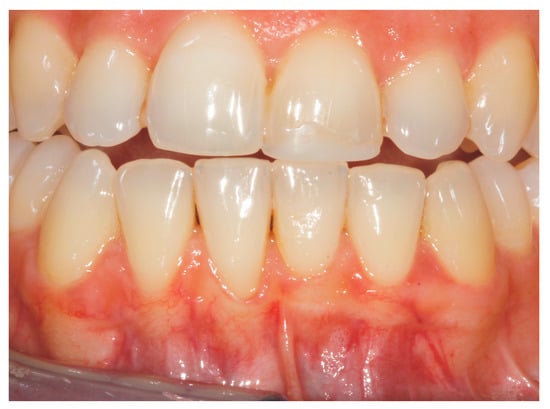

2. Case Study